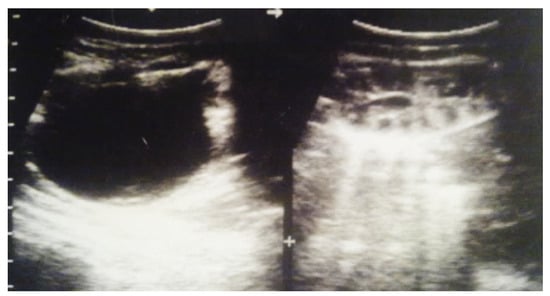

Figure 6. Ultrasound of the postnatal urinary system 10 days after birth. Hydronephrosis on the right.

Figure 7. Postnatal urinary ultrasound. Hydronephrosis on the right (newborn 10 days of age).

Our experience with congenital malformations of the urinary system refers to the following clinical case (Figure 2, Figure 3, Figure 4, Figure 5, Figure 6, Figure 7, Figure 8 and Figure 9). In the first case, during pregnancy, the 21-week ultrasound determined bilateral renal pyelectasia. The fetus had hydronephrosis on the right; at 31 weeks, it had bilateral hydrocalconephrosis; and at 32 weeks, bilateral pyelectasia. It suffered premature birth at 36 weeks, with complicated anomalies of the forces of contraction, prolonged birth, and birth weight of 2200 g. Postnatal ultrasonography was supplemented by intravenous urography, and bilateral hydronephrosis was determined. Hydrocalconephrosis on the left was discovered. The complete diagnosis was established: congenital renal malformation; bilateral pyelectasia; bilateral hydronephrosis; hydrocalconephrosis on the left; and severe reduced glomerular filtration rate (GFR), GFR > 2SD below mean.